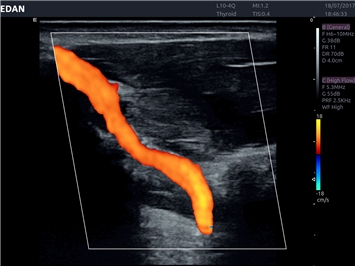

• Сосудистой диагностики

Цветовой допплер:

Да

Дуплексное сканирование: